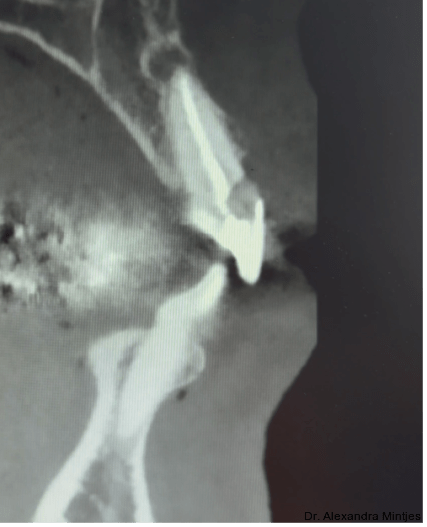

Bei der Erstvorstellung zeigte die vorhandene Füllung einen deutlichen Randspalt, war verfärbt und nach apikal hin insuffizient. Klinisch präsentierte sich ein dicker gingivaler Phänotyp mit ­harmonischer Weichgewebsbalance, jedoch bestand distal eine lokalisierte, entzündliche Zahnfleischtasche (Abb. 1). Es war zu vermuten, dass das nekrotische bzw. resorptive Hartgewebe nicht vollständig entfernt worden war. Auf dem DVT wurde das Ausmaß des Defekts deutlich. Zu­dem ließ sich eine deutliche apikale Aufhel­lung nachweisen, die Patientin war jedoch beschwerdefrei (Abb. 2).

Die Diagnose lautete eine invasive zervikale Resorption Klasse 3 nach Heithersay. Dieses Sta­-dium beschreibt eine tiefe Resorption mit Ausdehnung in das koronale Dentin und das zervikale Drittel der Wurzel, ohne dass die Pulpa vollstän­dig involviert ist. Solche Läsionen gelten als prognostisch kritisch und führen in der Regel zu einer extraktiven Therapie.